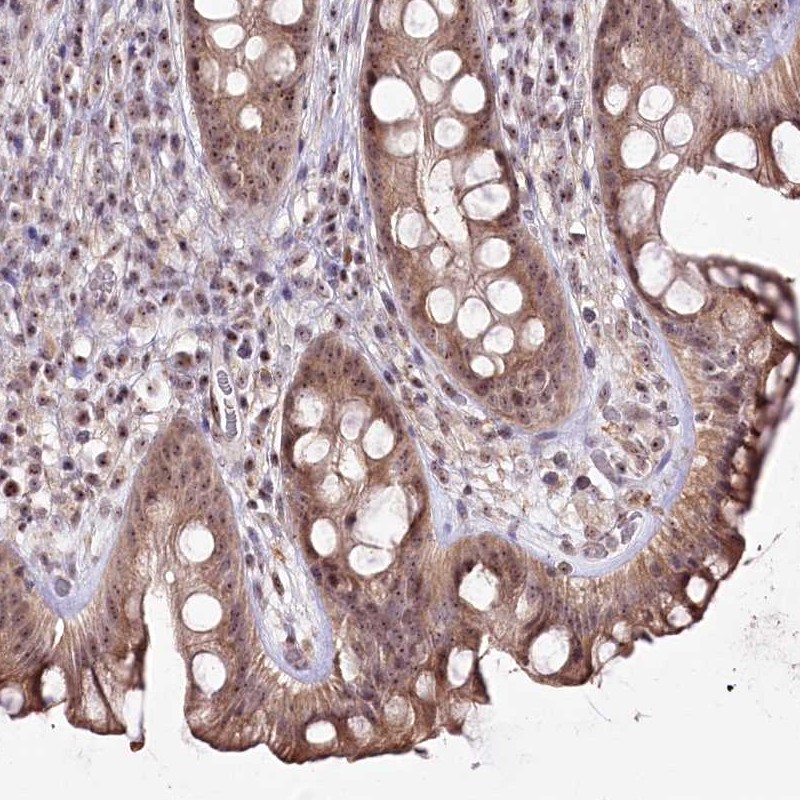

Immunohistochemical staining of human rectum shows moderate cytoplasmic and nucleolar positivity in glandular cells.